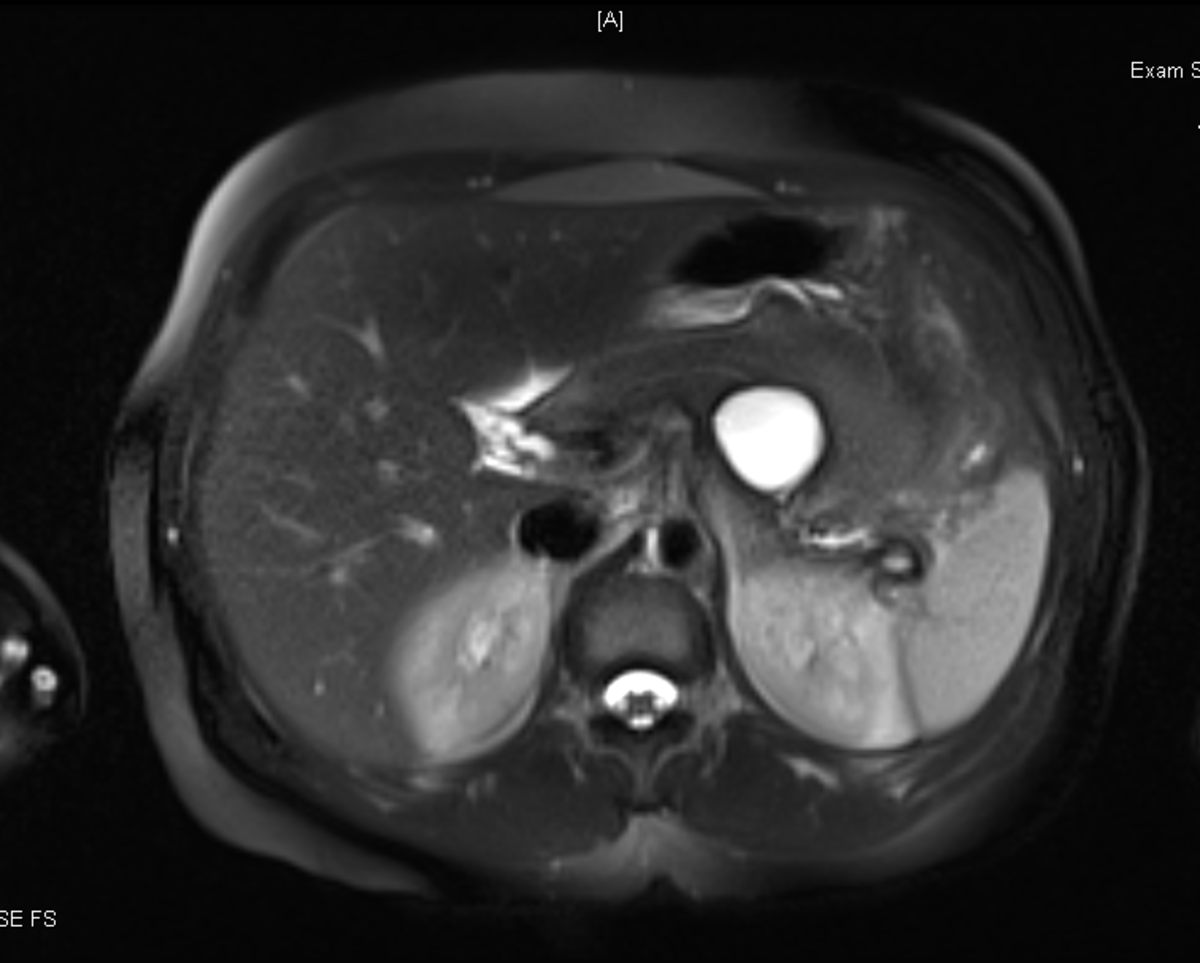

Computed tomography of the abdomen/pelvis with IV contrast was obtained [figures A and B]. What should be your next step in management?

• Surgery consultation is the best next step in this patient with septic shock due to acute calculous cholecystitis, now complicated by suspected gallbladder perforation. The CT images demonstrate a rim of enhancement along the hepatic capsule (Figure A arrows: peritonitis) and a defect in the gallbladder wall (Figure B arrow: perforation). The gallbladder otherwise shows classic findings of acute cholecystitis, including gallbladder wall thickening, pericholecystic fluid/stranding, and enhancement of the gallbladder mucosa. Emergency exploratory laparoscopy with the possibility of conversion to open exploration is indicated. Frequently, abdominal cavity washout and surgical drain placement are needed.

Initial nonoperative management with antimicrobials is recommended over immediate cholecystectomy for American Society of Anesthesiologists (ASA) classification III or IV patients with acute calculous cholecystitis who lack an indication for emergency cholecystectomy (i.e., operative risks outweigh benefits). Nonoperative gallbladder drainage is warranted among high-risk patients (ASA III/IV) who fail to clinically improve after 1-3 days of medical management, given that cholecystectomy is associated with ≤19% mortality rate in high-risk patients. Failure to improve after nonoperative biliary drainage requires re-evaluation of drain positioning and careful review for complications of acute cholecystitis. Regardless of surgical risk, emergency cholecystectomy is indicated for complicated acute cholecystitis (e.g., gallbladder necrosis, gallbladder perforation, or emphysematous cholecystitis).